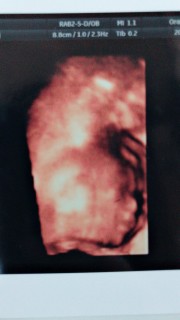

8割女の子だと言われました! 毎日胎動もすごくておてんばさんになるのかな☆初めて3Dでお顔を見れて皆からパパ似って言われて超ご機嫌の旦那さん(笑) 405gでした。

初めて4Dエコーを見ました。うつ伏せに寝ていたので顔は見れなかったけど、順調に成長してくれていました。